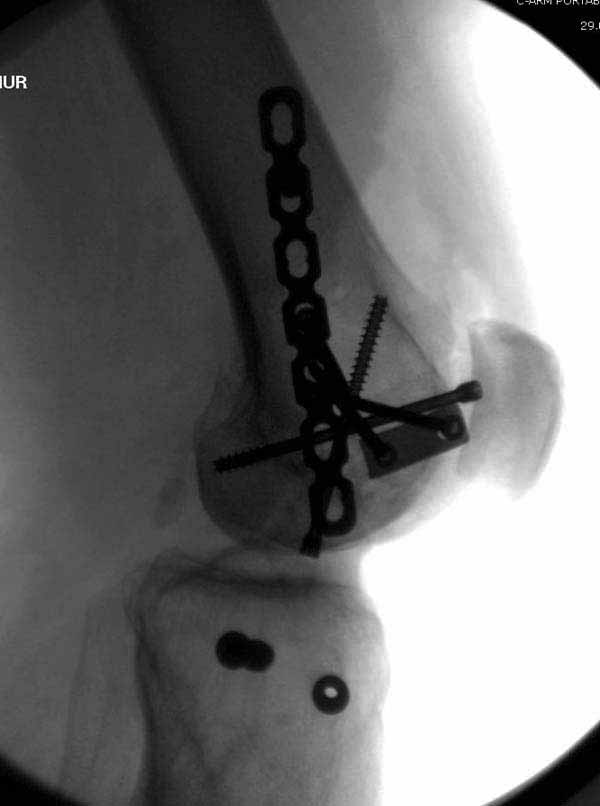

В приложении пример недавней операции, C3, открытая репозиция, фиксация мыщелков спицами и винтами, ретроградный синтез большеберцовым гвоздем 10,5 мм диаметром, винты 5 мм.

Позволю себе напомнить коллегам ещё раз, что являюсь сторонником антеградного остеосинтеза при переломах дистального эпиметафиза бедренной кости. Такая приверженность основана не на преимуществах внесуставного введения стержня или большем проценте положительных результатов. Она основана на возможности обеспечить блокирование на минимальном расстоянии от суставной поверхности в нескомпрометированной кости и, таким образом стабилизировать максимально низкие переломы. В приведенном Вами случае самый дистальный из блокирующих винтов проведен на расстоянии более 2 см от конца стержня. Из-за того, что к стержню присоединяется кондуктор, на стержне теряется 1-1,5 см его длины, где можно было разместить отверстия для блокирования. И что более важно, вместе с потерянной для этой цели длиной стержня утрачивается для размещения блокировочных винтов, пожалуй, самая ценная часть дистального эпиметафиза бедренной кости. Проблемы дистального блокирования в разных плоскостях, локализации точки ввода стержня при антеградном остеосинтезе – это всё решаемые технические проблемы. Но антеградный остеосинтез низких дистальных переломов бедра при адекватном блокировании в нескомпрометированной кости обеспечивает решение стратегической задачи – стабильный остеосинтез и возможность нагрузки.

На этом большеберцовом стержне центр ближайшего к кондуктору отверстия в 14 мм от конца. И пример был про то, что пластина тут, скорее всего, была бы не худшим выбором.